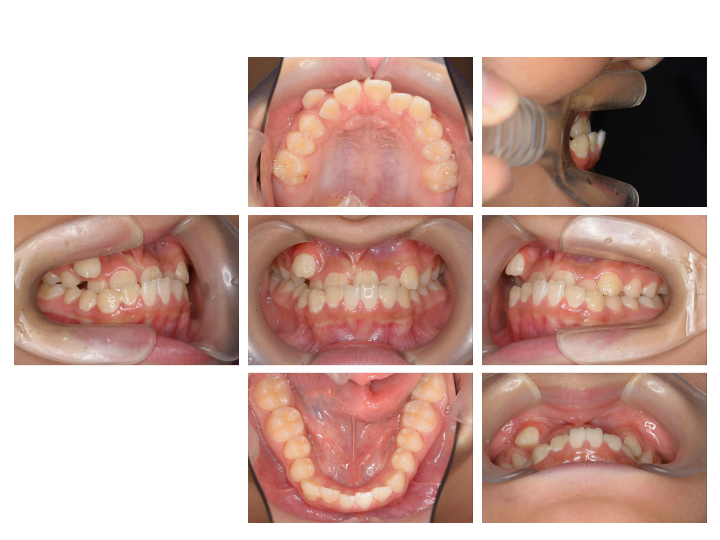

実は小児矯正とはいっても、一般的には成人矯正までかかることが多くあります。

日本の小児矯正のおよそ7割は、成人の抜歯矯正になるため、期間にすると、矯正を始めてからおよそ10年かかることになります。

小学生から始めて大学生までかかる長期治療となります。

ですが、当院の「骨格にフォーカスした矯正」ならほとんどが小児矯正(およそ2年)で終わります。